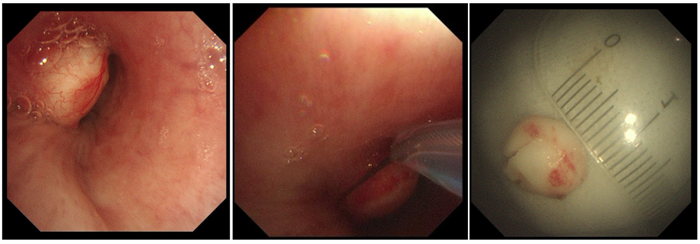

2月15日,由于世倫副院長親自操作,在狄紅紅主治醫師、田忠敏護士長協助下,成功為患者行高頻電套扎切除結節狀白色腫物。

患者左主支氣管遠端見結節狀白色腫物,表面上有少許表淺血管顯露,基底較寬,堵塞管腔約70%,予以高頻電套扎切除,少許出血,給與局部噴灑腎上腺素溶液止血,標本送病理。2月16日病理結果示:肺錯構瘤。患者于2月16日出院,醫護人員就復診問題給予其詳細的指導。